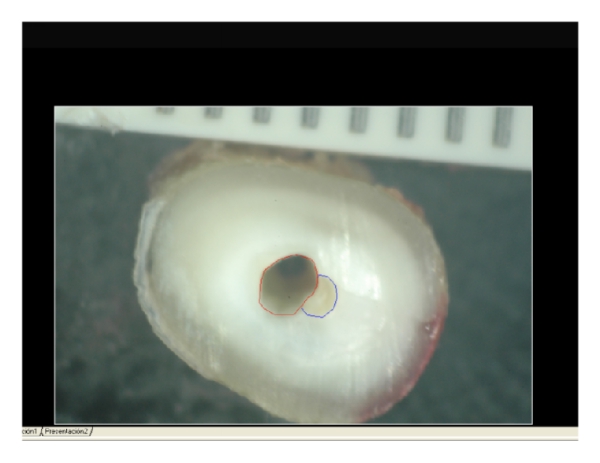

The next step was to cut the root portion of each of the samples with a 0.2 mm thick blade into three sections: the apical third, the middle third, and the coronal third (Figure 1).

After that, the root section of each sample was studied under a Nikon SMZ 2T stereo microscope at 100x magnification. As the microscope includes a Nikon D70 camera on top, each section was photographed so as to be able to compare it once the canal had been prepared.

Subsequently, the surface areas in mm2 were measured before and after instrumentation using Autocad analytical software (Figure 3).